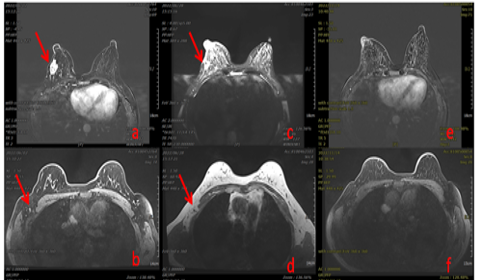

50岁,右侧乳腺恶性肿瘤Luminal A型 T2N2M0 ⅡB期,a.碳离子治疗前,乳腺肿瘤最大径32mm;b.碳离子治疗前,腋窝淋巴结转移病灶最大径9mm;c.治疗后乳腺肿瘤最大径19mn;d.治疗后,腋窝淋巴结最大径4mm;e.治疗后4月,乳腺肿瘤消失;f.治疗后4月,腋窝淋巴结消失。